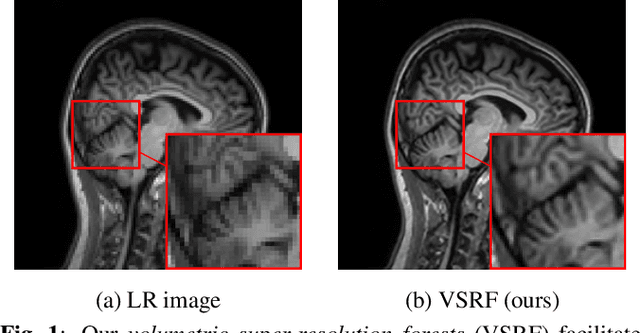

Abstract:Magnetic resonance imaging (MRI) enables 3-D imaging of anatomical structures. However, the acquisition of MR volumes with high spatial resolution leads to long scan times. To this end, we propose volumetric super-resolution forests (VSRF) to enhance MRI resolution retrospectively. Our method learns a locally linear mapping between low-resolution and high-resolution volumetric image patches by employing random forest regression. We customize features suitable for volumetric MRI to train the random forest and propose a median tree ensemble for robust regression. VSRF outperforms state-of-the-art example-based super-resolution in term of image quality and efficiency for model training and inference in different MRI datasets. It is also superior to unsupervised methods with just a handful or even a single volume to assemble training data.